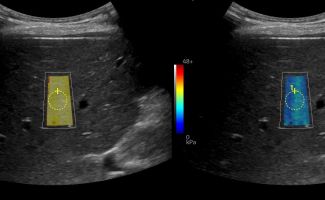

Με την Eλαστογραφία Ήπατος γίνεται αξιολόγηση της ελαστικότητας του ήπατος και υπολογισμός του βαθμού λιπώδους διήθησης ή/και ίνωσης, σε περίπτωση χρόνιας ηπατοπάθειας.